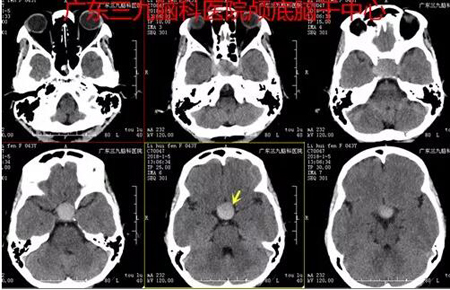

▲图1:2018-01-05 术前CT示鞍区内示一团块状稍高密度影,范围约3.2cm×2.7cm×2.1cm